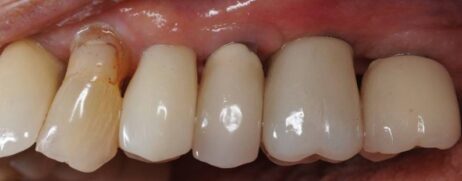

Routine model work was completed by switching back to the M1.6 impression bolt and using a stock Straumann analog. A custom abutment was fabricated by Staumann AXS (formally Scan and Shape). Once received, the abutment through bore was tapped to M1.8 and a zirconia crown was made to be delivered screwmentable. The two impressions made of the implant, post tapping, were nickelsulfamate plated to create two custom pure nickel dies. These dies were sectioned, one completely and the other just in the end threads and used to verify the exact thread length needed when the new M1.8 abutment screw was made. The abutment screw was made from Ti6Al4V ELI alloy from Carpenter alloys (Cartech). The case was then delivered as a routine screwmentable delivery with the new abutment screw double torqued to 35Ncm.